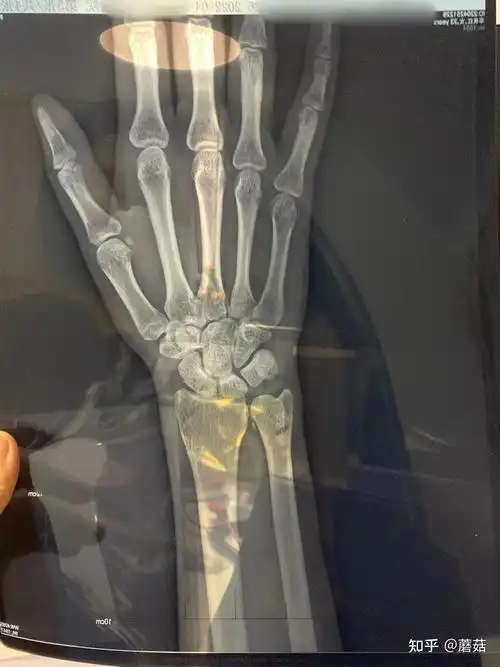

翻出了期间的各种片子,报告,开始研究,结果看到了手腕x光片的报告,尺